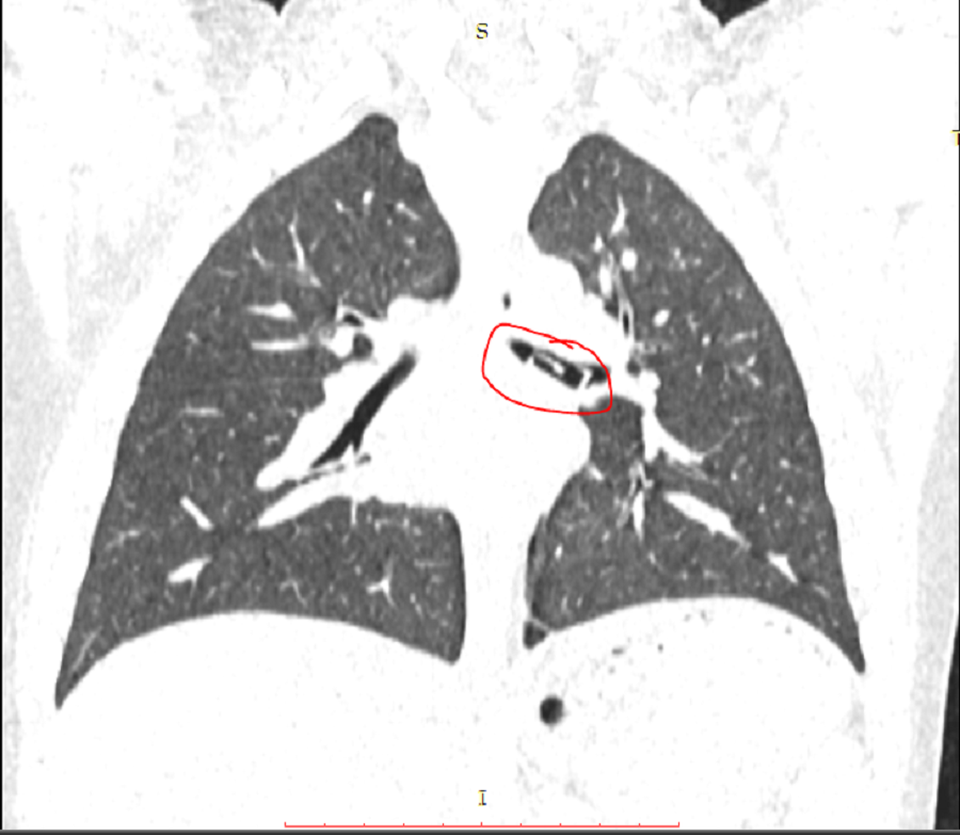

Trưa 7/3, bé D. được chuyển đến Bệnh viện Quận Thủ Đức cấp cứu trong tình trạng ho sặc sụa, tím tái. Bệnh nhi được bác sĩ kiểm tra, phát hiện khối dị vật trong phế quản.

Hình ảnh kiểm tra phát hiện dị vật nằm trong phế quản của bệnh nhi

Sau hội chẩn, các bác sĩ quyết định nội soi gắp dị vật ở phế quản trái cho bệnh nhi.